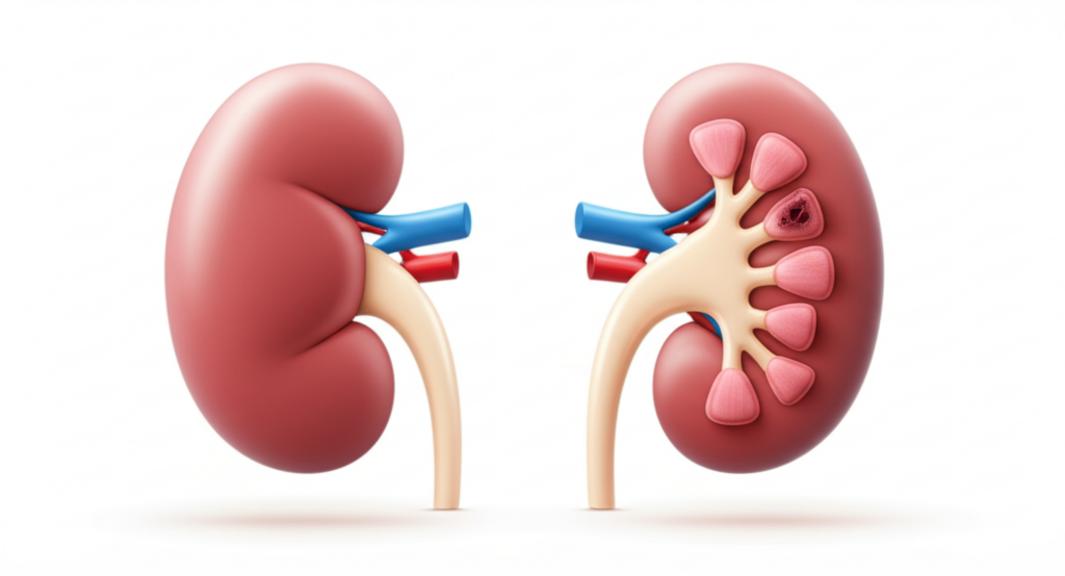

ความเสื่อมของไตตามวัยเป็นกระบวนการที่ซับซ้อน แต่เวชศาสตร์ชะลอวัยชี้ให้เห็นว่าปัจจัยหลายอย่างมีอิทธิพลเร่งให้เกิดความเสียหายก่อนวัยอันควร เซลล์ไตประกอบด้วยหน่วยกรองเล็กๆ นับล้านหน่วยที่เรียกว่า “เนฟรอน” ซึ่งมีหน้าที่สำคัญในการกรองเลือดและสร้างปัสสาวะ เมื่อเราอายุมากขึ้น จำนวนเนฟรอนเหล่านี้มีแนวโน้มลดลง และเนฟรอนที่เหลือก็อาจทำงานได้ไม่เต็มที่นัก ปัจจัยหลักที่กระตุ้นให้เกิดความเสื่อม ได้แก่: